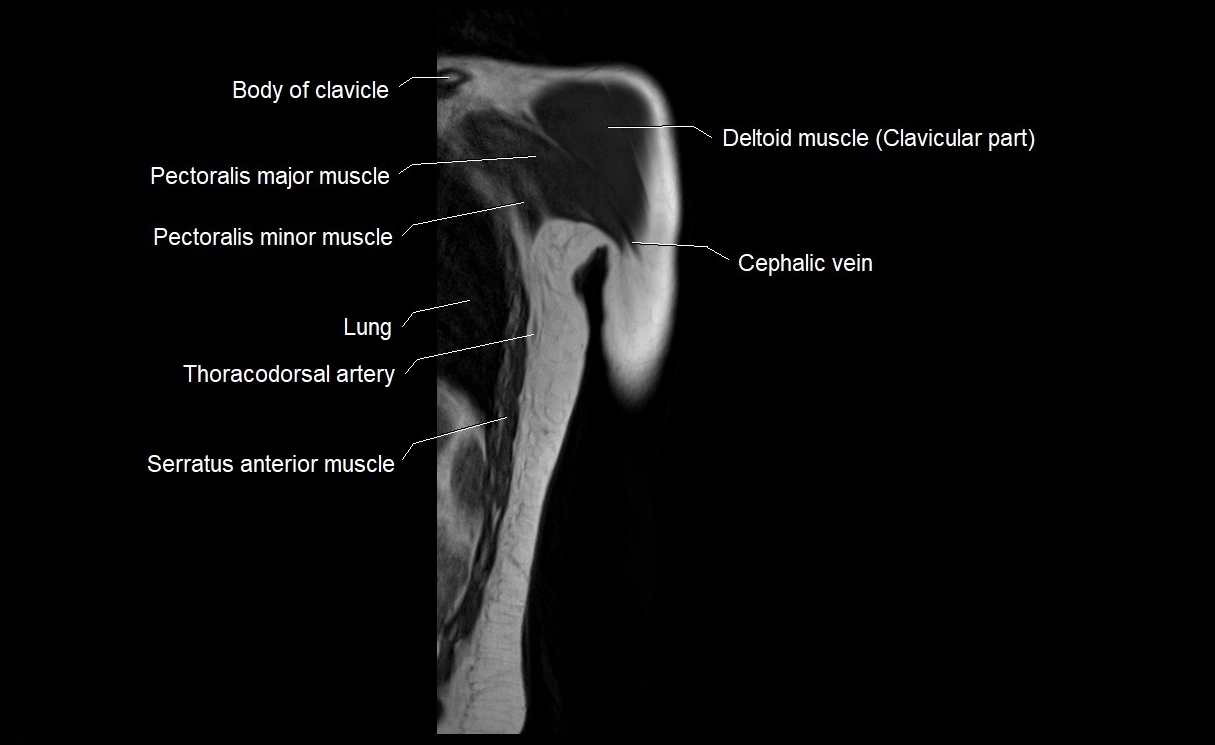

- Cephalic vein

- Clavicular part of deltoid muscle

- Pectoralis major muscle

- Pectoralis minor muscle